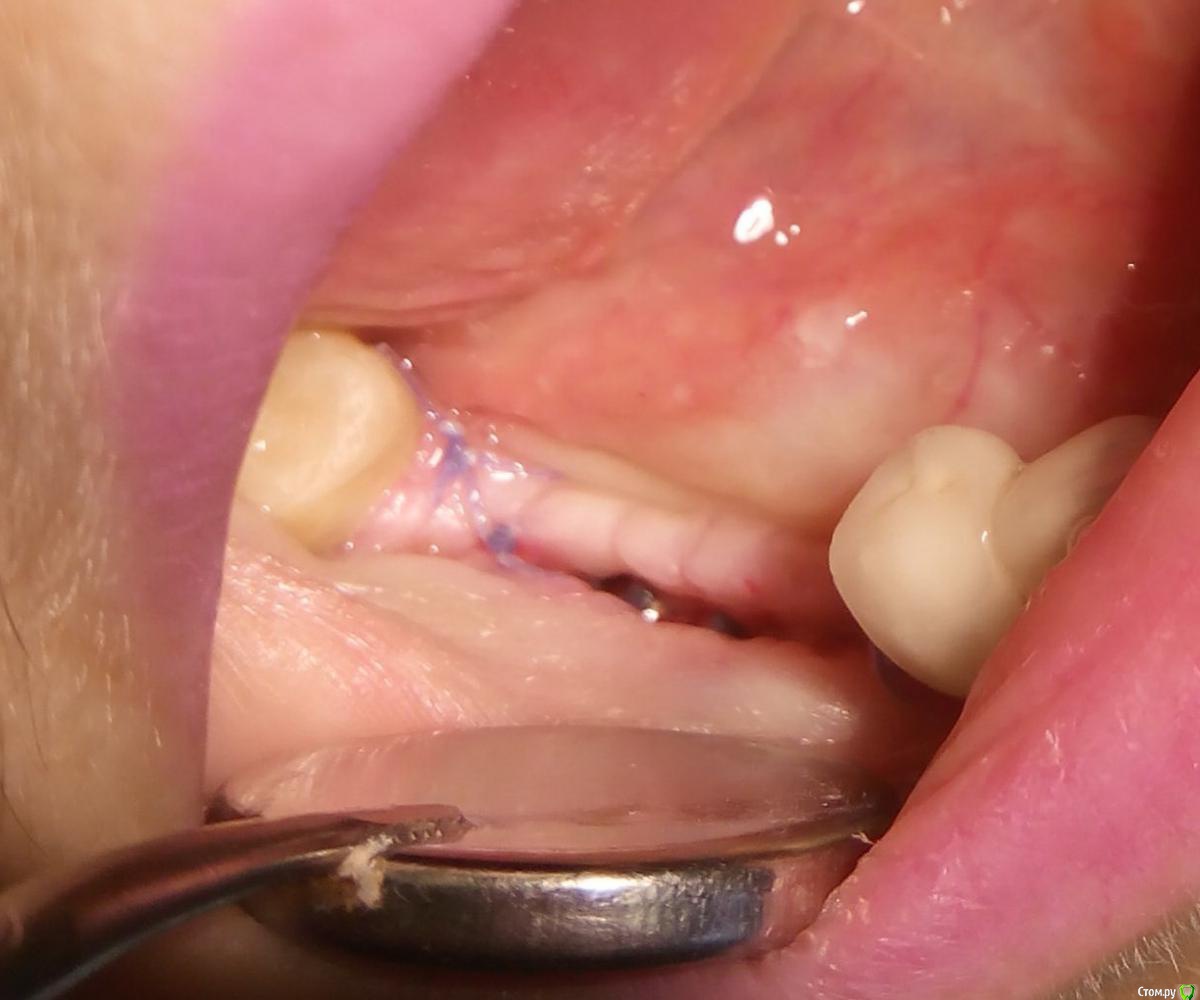

syrovovec Опубликовано 10 июля, 2015 Автор Поделиться Опубликовано 10 июля, 2015 Примерно через 2 недели, затянулось вторичкой http://s017.radikal.ru/i432/1507/74/2341618392db.jpg 3 Ссылка на комментарий